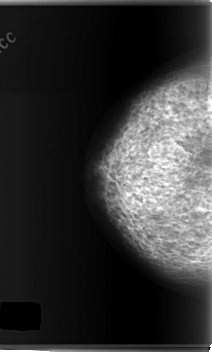

C_0148_1.LEFT_CC

LEFT_CC LINES 6008 PIXELS_PER_LINE 3592 BITS_PER_PIXEL 12 RESOLUTION 50 OVERLAY

FILE: C_0148_1.LEFT_CC.OVERLAY

TOTAL_ABNORMALITIES 1

ABNORMALITY 1

LESION_TYPE MASS SHAPE ARCHITECTURAL_DISTORTION MARGINS ILL_DEFINED

ASSESSMENT 4

SUBTLETY 2

PATHOLOGY MALIGNANT

TOTAL_OUTLINES 1

BOUNDARY